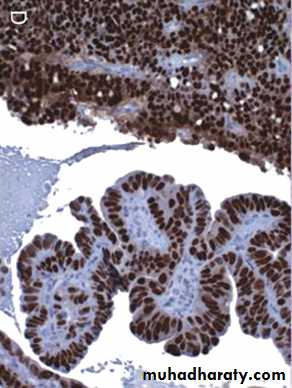

C, displaying formation of papillae and marked cytologic atypia. D, Immunohistochemical stain for p53 reveals accumulation of mutant p53 in serous carcinoma.

Serous carcinoma of the endometrium